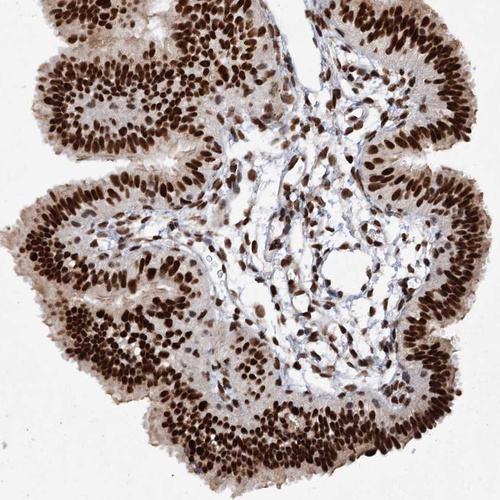

Immunohistochemical staining of human cerebral cortex shows strong nuclear positivity in neurons.